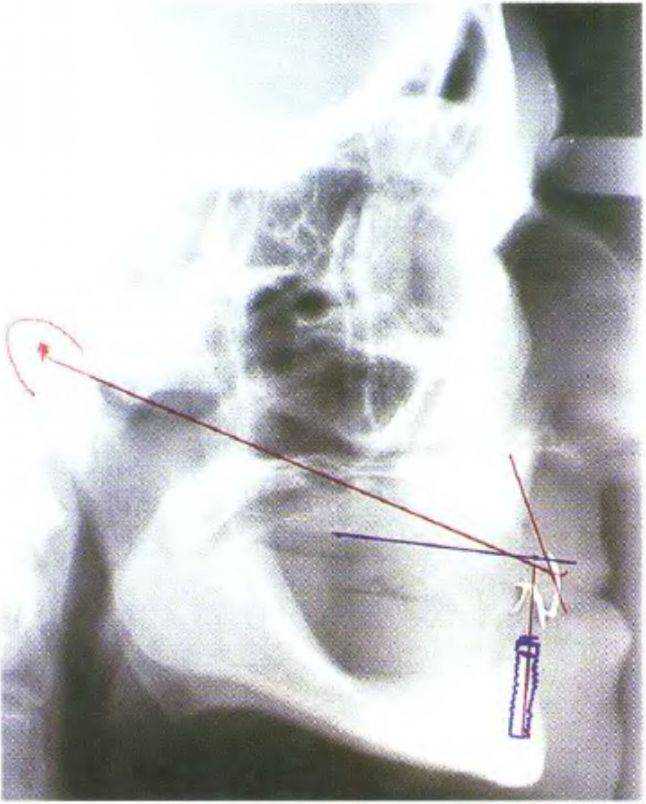

Рис. 3-44. «Среднесагиттальная томография» представляет собой участок боковой цефалограммы

Рис. 3-45а. На боковой цефалограмме визуализируются вестибулярные и небные контуры передних зубов, покрытых фольгой

Рис. 3-45Ь. Функциональный анализ цефалограммы

Одним из наиболее эффективных способов является боковая цефалограмма с фиксированной к передним зубам полоской свинцовой фольги (как описано ранее в данной главе и главе 6). Такой снимок позволяет провести анализ переднего отдела нижней и верхней челюсти, а также определить наклон имплантата и высоту кости. Кроме того, с помощью боковой цефалограммы можно выполнить сагиттальный функциональный анализ (рис. 3-45а и 3-45Ь). На рис. 3-46 представлены варианты сечения нижней челюсти в ее переднем отделе в зависимости от степени атрофии. Обычно плотность костной ткани в данном участке соответствует классу D1.